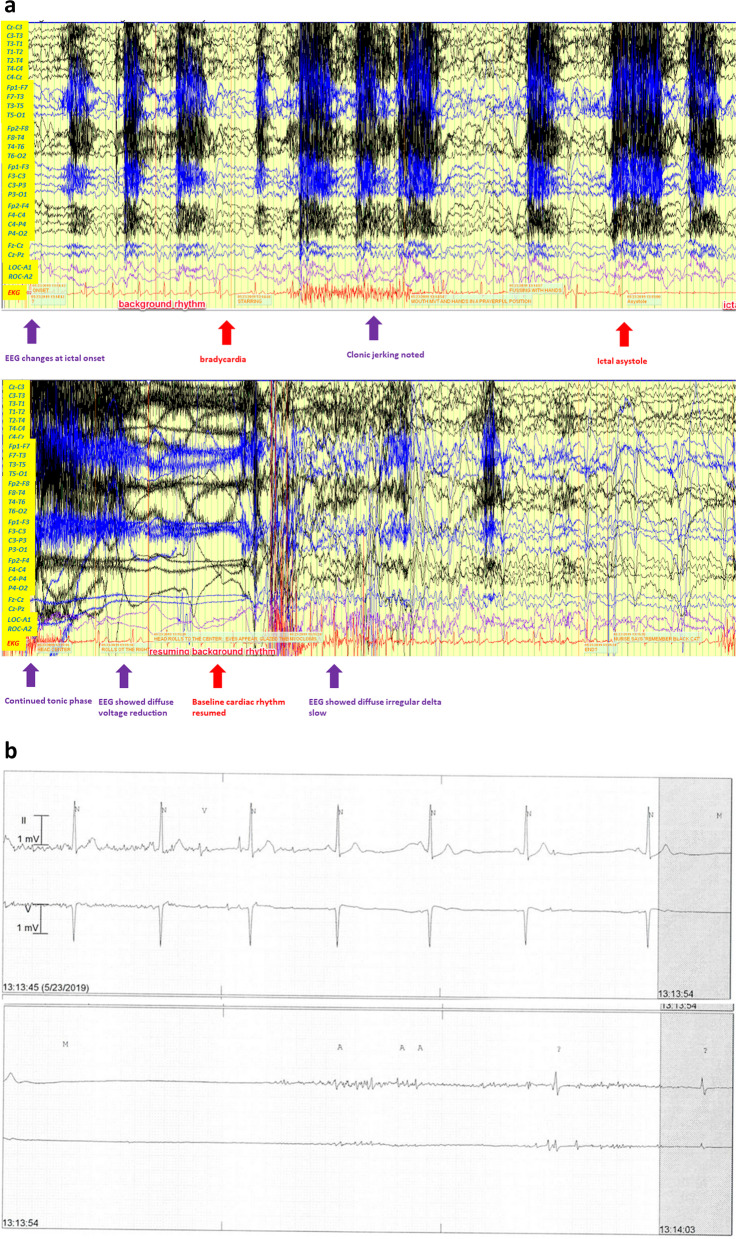

Case presentation: We present a 35-year-old man with a history of focal-onset seizures with impaired consciousness since his mid-20 s. He developed different types of seizures for 2 years, described as tonic seizure and atonic seizure (drop attack). During such clinical events, he suffered from falls and cardiac arrest. However, thorough cardiac electrophysiology and imaging workup failed to reveal a cardiac etiology. Subsequent video electroencephalograph (EEG) monitoring was performed, and ictal bradycardia and ictal asystole were discovered. A cardiac pacemaker was implanted, and at 3-year follow-up, the patient did not suffer more atonic seizures, or falls. Genetic tests discovered a de novo variant of Adhesion G Protein-Coupled Receptor V1 (ADGRV1), which may provide a clue for the patient's ictal asystole and the increased risk of SUDEP.

Conclusions: Considering the important impact of ictal bradycardia and asystole on the morbidity and potential mortality of epileptic patients, it is important to simultaneously utilize EEG and electrocardiogram to confirm the diagnosis. This case report highlights the link between the de novo variant of ADGRV1 and the ictal bradycardia/asystole phenotype and implicates the importance of genetic testing in adult epilepsy patients.